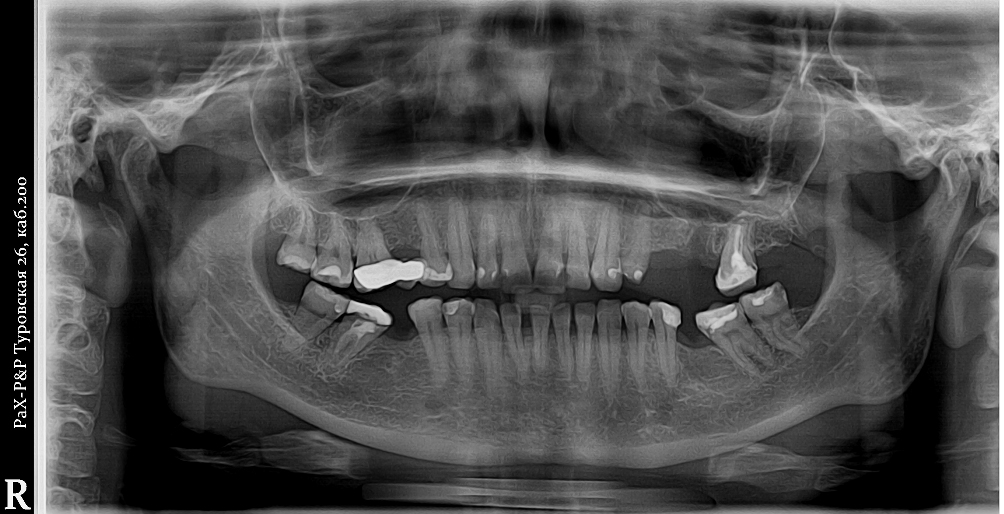

Преимущества и недостатки панорамных снимков

Преимущества

- Малая доза лучевой нагрузки – 70 мкЗв (микроЗиверт).

- Быстрота — ОПТГ готов уже через 5-9 секунд.

- Много информации на одном снимке — видны все зубы с корнями, обе челюсти, гайморовы пазухи, височно-нижнечелюстные суставы, частично даже полость носа.

Недостатки

- Двухмерный вид не даёт информацию во всех плоскостях — для этого нужен 3D КТ снимок.

- Недостаточно чёткое отображение мелких деталей.

- Искажения, наслоение теней от других костей и позвоночника, смещения и затемнения неизбежны.

- Лишь ориентировочное представление о размерах корней зубов и расстоянии до важнейших анатомических образований (канал нижнечелюстного нерва и гайморова пазуха), из-за того, что изображение растянуто неравномерно в боковых и передних отделах.

Когда нужны панорамные снимки?

Ортопантомограмма быстро даёт большой объём информации о пациенте, что обуславливает её универсальность и широкое применение в различных отраслях стоматологии:

- Первичная диагностика – проводится на первичном стоматологическом приеме пациенту любого возраста.

- Ранняя диагностика аномалий зубочелюстной системы – по мировым стандартам рекомендуется проходить плановую ОПТГ для обнаружения одонтогенных (зубных) кист, пороков развития и опухолей в 10, 15, 20 лет.

- Терапевтическая стоматология – помогает оценить качество пломбировки корневых каналов, расположение пломбы по отношению к пульпе зуба, наличие воспаления за пределами корней.

- Хирургическая стоматология – даёт представление о форме и количестве корней перед удалением зубов, перед удалением зубов мудрости (в том числе ретенированных), а также перед удалением кист зубов.

- Имплантология – начальное планирование имплантации до 3D КЛКТ снимка, контроль за приживлением имплантов и костного графта после выполнения синус-лифтинга.

- Ортопедическая стоматология – в качестве диагностики состояния зубов и их корней перед планированием любого вида протезирования зубов и протезирования имплантов.

- Ортодонтия – определение наличия зубов мудрости перед планированием брекет-системы, контроль отработки параметров торка и параллельности корней на этапах ортодонтического лечения.

- Детская стоматология – определения положения зачатков постоянных зубов.

- Травма – ортопантомограмма позволяет выяснить, произошел ли перелом челюсти или зубов в результате травмы.